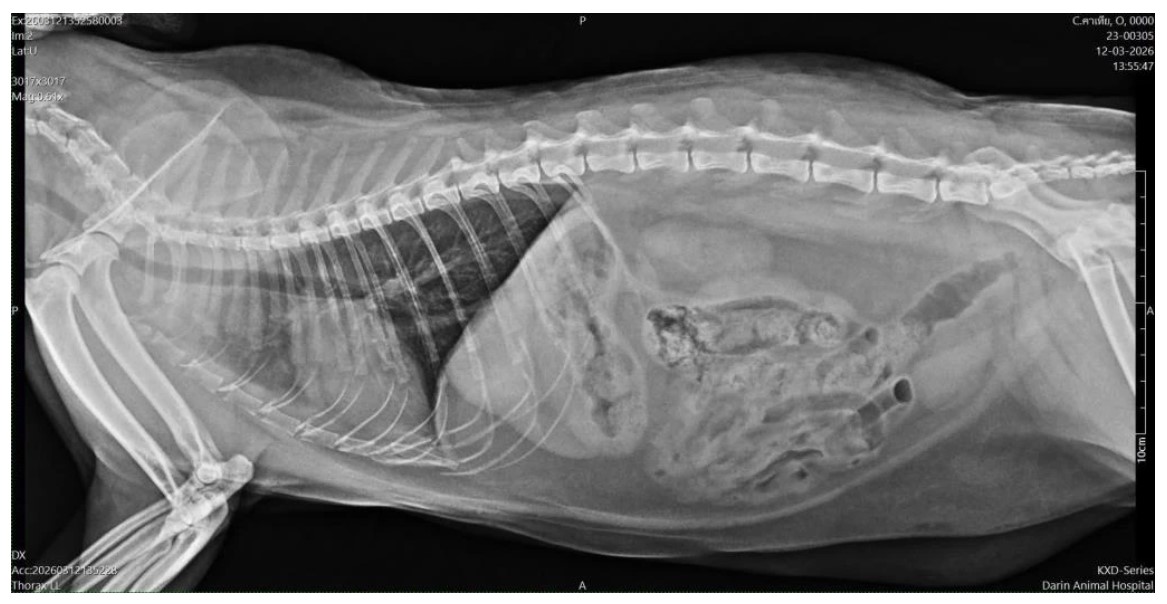

จนวันหนึ่งถึงคราวตรวจสุขภาพประจำปี เอกซเรย์แล้วพบปอดอักเสบแบบเข้าขั้นเยอะ ถึงเยอะมากเลยล่ะ

จากภาพจะมีบริเวณที่เป็นฝ้าขาว ด้านซ้ายของรูป ใต้กระดูก *คุณหมอจะอ่านภาพและชี้จุดให้